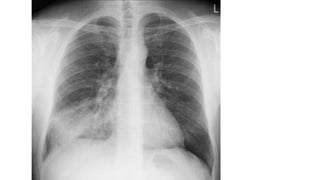

F-Lung Fields

• Normally, there are visible markings throughout the lungs

due to the pulmonary arteries and veins, continuing all the

way to the chest wall.

• Both lungs should be scanned, starting at the apices and

working downward, comparing the left and right lung fields

at the same level.

F-Lung Fields • Normally,there are visible markings throughout the lungs due to the pulmonary arteries and veins, continuing all the way to the chest wall. • Both lungs should be scanned, starting at the apices and working downward, comparing the left and right lung fields at the same level.